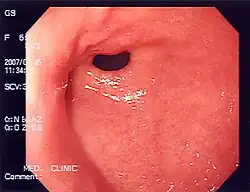

Medizinische Endoskopie

Medizinische Endoskope haben die Untersuchung des Magen-Darmtraktes, der Lunge und auch der Gebärmutter revolutioniert. Sogar die ableitenden Tränenwege können endoskopisch untersucht werden.

Die ältesten und einfachsten noch im Gebrauch befindlichen Endoskope bestehen aus einem starren Rohr, durch welches das notwendige Licht hineingespiegelt wird und wodurch man mit dem bloßen Auge sieht. Daher spricht man volkstümlich von „Spiegelung“. Die längeren Geräte waren zusätzlich mit Linsen in einem Schlauch am vorderen Ende ausgestattet und ermöglichten erstmals passiv geringe Bewegungen.

Eine erste Weiterentwicklung bestand darin, ortsfern erzeugtes Licht mit Glasfaserbündeln an die Rohrspitze zu bringen. Der nächste Entwicklungsschritt war, auch die Bildinformation über flexible, geordnete Glasfaserbündel, die Bildleiter, zum Auge des Untersuchers zu übertragen. Erst hiermit wurde das Endoskop wirklich flexibel. Die aktive Steuerung des Gerätes erfolgt seither über vier eingearbeitete Bowdenzüge.

Heutzutage wird, vor allem unter stationären Bedingungen, das Bild nicht mehr direkt mit dem Auge (weder am starren Rohrendoskop, noch am Okular des flexiblen Endoskops) betrachtet, sondern an einem oder mehreren modernen Monitoren, die die Farbinformation möglichst wenig verfälschen, und die die Arbeit und das Lehren (Kibitzen) ohne Qualitätsverlust bei Tageslicht ermöglichen. Dadurch eröffnet sich zusätzlich auch die Möglichkeit der Aufzeichnung auf Videoträger oder eine Übertragung in Hörsäle.